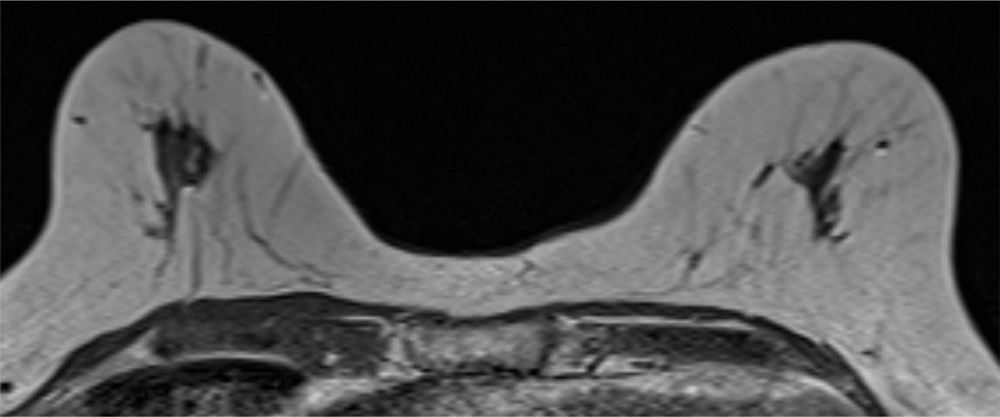

2. T2強調画像

病変は周囲乳腺実質と比較して軽度低信号を呈している。

3. T1強調画像

病変は周囲乳腺実質と等信号で同定が困難である。